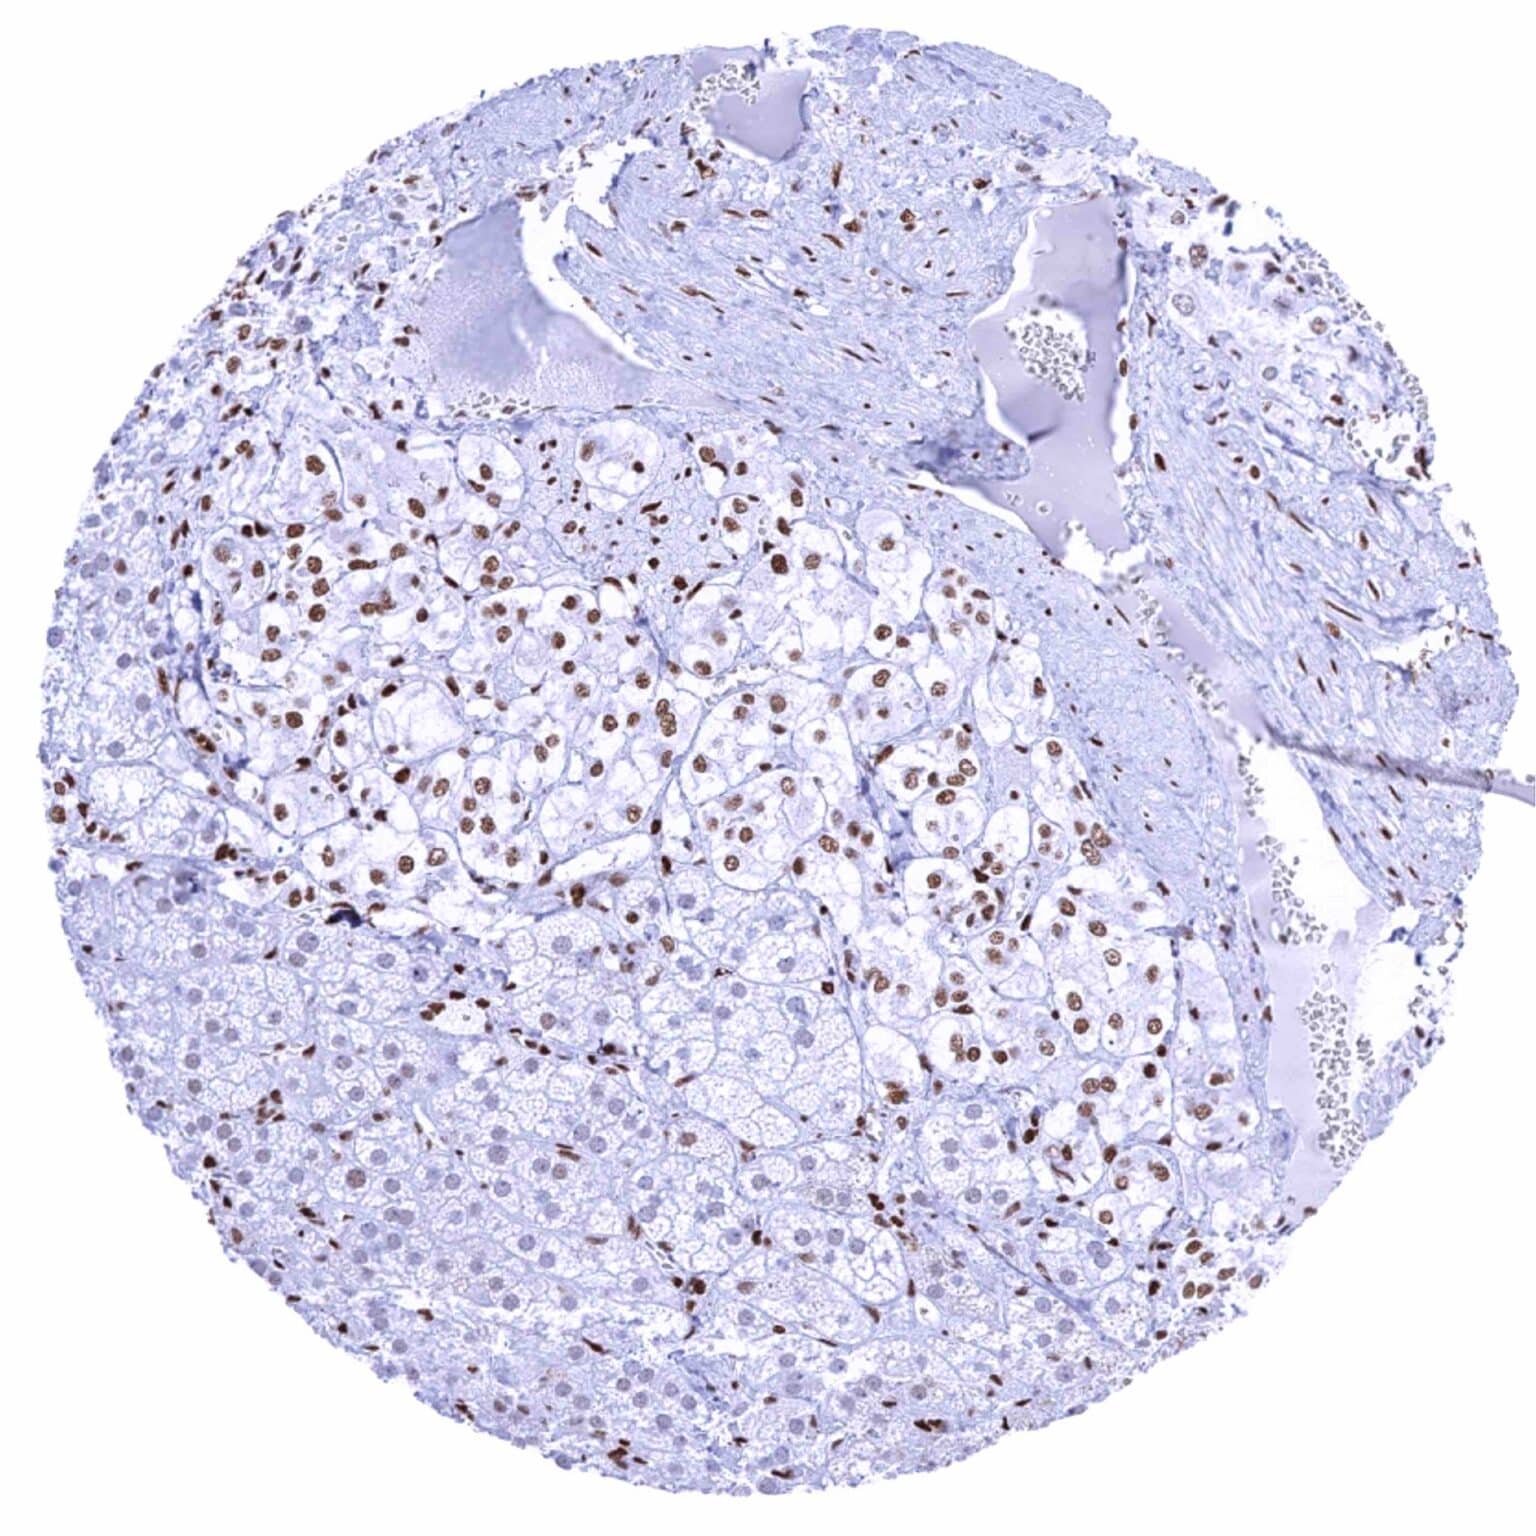

Pancreas – Moderate to strong GR positivity of acinar cells while islet cells show a strong staining